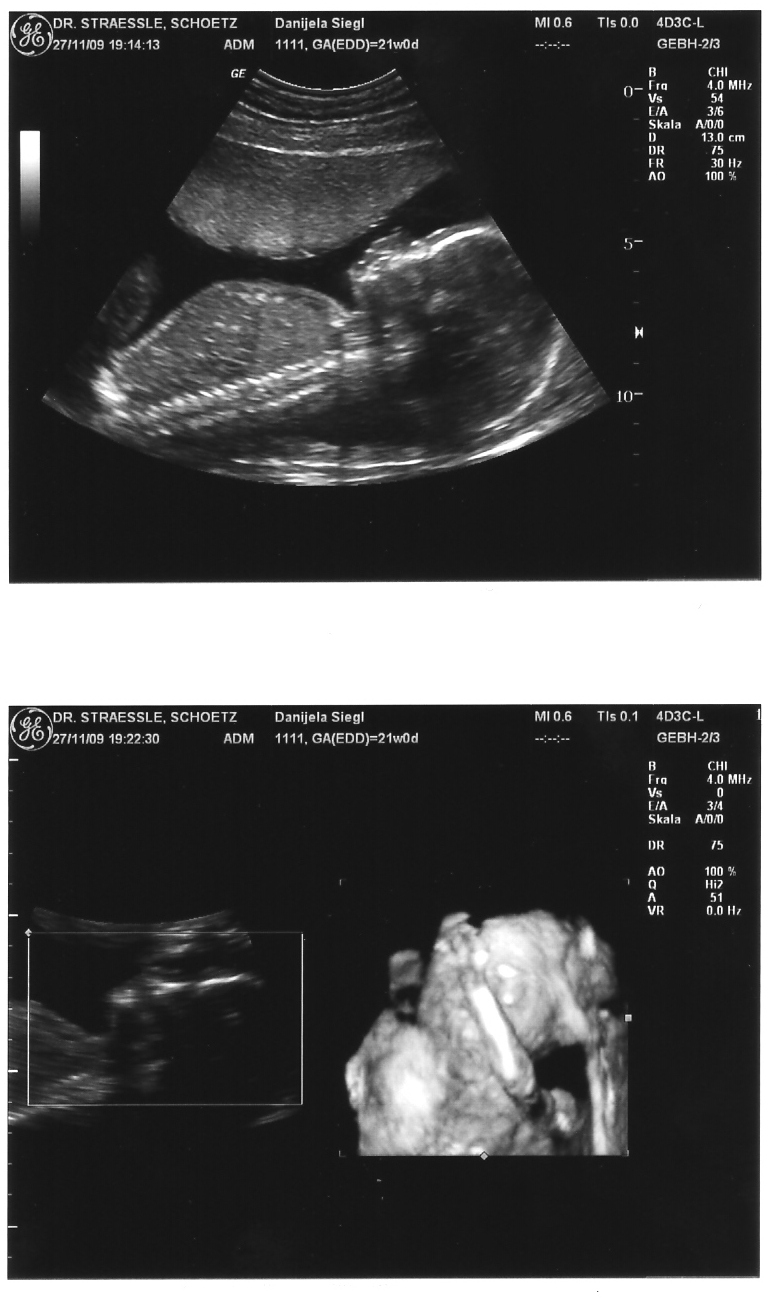

ja wir waren am Freitag beim Baby-watching

der Doc meinte er kann es noch nicht genau sagen ob es boy oder girl wird - ich hab aber alles gefilmt und mehrmals angeschaut und ich denke mal bei einem Jungen müsste man was zwischen den Beinen sehen - da war aber nix

schaut ganz nach Mädchen aus

das rechts ist ein 3D-Bildt, leider hält "es" sich gerade die Hand vors Gesicht - wollte wolh nicht gesehen werden

sieht ech süss aus...nochmals glückwümsche